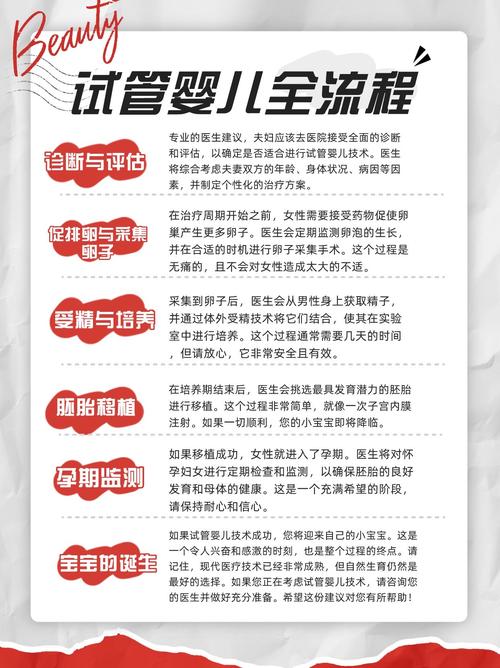

母体因素也是导致胚胎培养失败的重要原因。根据《生殖医学杂志》2023年的统计,约有20%的试管婴儿失败是因为母体因素。这些因素包括子宫内膜异常、内分泌失调等。

2. 改善母体环境

改善母体环境也是提高试管婴儿成功率的重要途径。可以通过以下方法来改善母体环境:

- 调整内分泌,改善子宫内膜环境

- 治疗子宫内膜异常,提高着床率

- 合理饮食、运动,提高母体整体健康状况